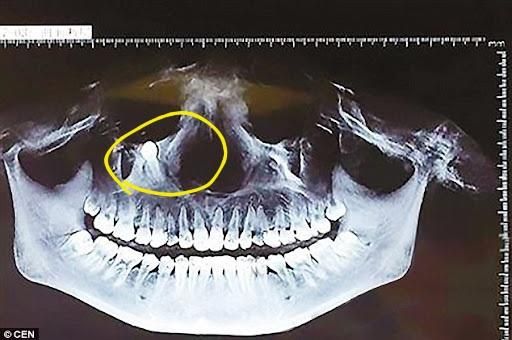

치아가 어쩌다 저기서 자라게 되는건가요?

무언가 큰 하자가 있어서 저런 곳에서 자라는건가요?

턱이 아닌곳에 위치한 치아도 정상 치아처럼 시간아 지나면 올라오게 될까요 그럼 눈에 장애가 생길까요?

유전적인 경우가 많습니다. 운이라기보다는 유전적인 영향으로 해당 부위에 치아가 매복되었다고 보시면 됩니다. 지금 사진으로는 과잉치인지, 매복치인지 알 수 없으나 과잉치가 맞다면 유전적인 영향이 거의 대부분입니다.

과잉치 입니다. 비정상적으로 치아가 하나더 생성되면서 자라날 공간이 없으니 위쪽으로 간겁니다. 저정도 깊이 잇다면 크게 문제가 되는건 아닙니다.

치아의 개수를 봤을 경우 송곳니가 잘못된 방향으로 시계가 형성되어 해당 부위로 이동한 것으로 보입니다. 현재 있는 송곳니는 유치일 가능성이 높습니다. 전환식의 위치에 있어도 크게 문제를 발생시키지 않는다면 발치를 하지 않아도 될 수 있습니다.

치아는 치아 새싹이라고 하는 치배에서 생성되는데 처음에 치배가 위치를 잘못 잡게 되면 그렇게 될 수 있습니다. 눈이 위치하고 있는 눈확에 가깝긴한데 뼈에 묻혀있어서 크게 눈 자체에 영향을 주진 않을 것 같고 주변 지나는 신경이나 혈관등과 근접하면 나중에 문제를 일으킬 가능성은 있습니다.